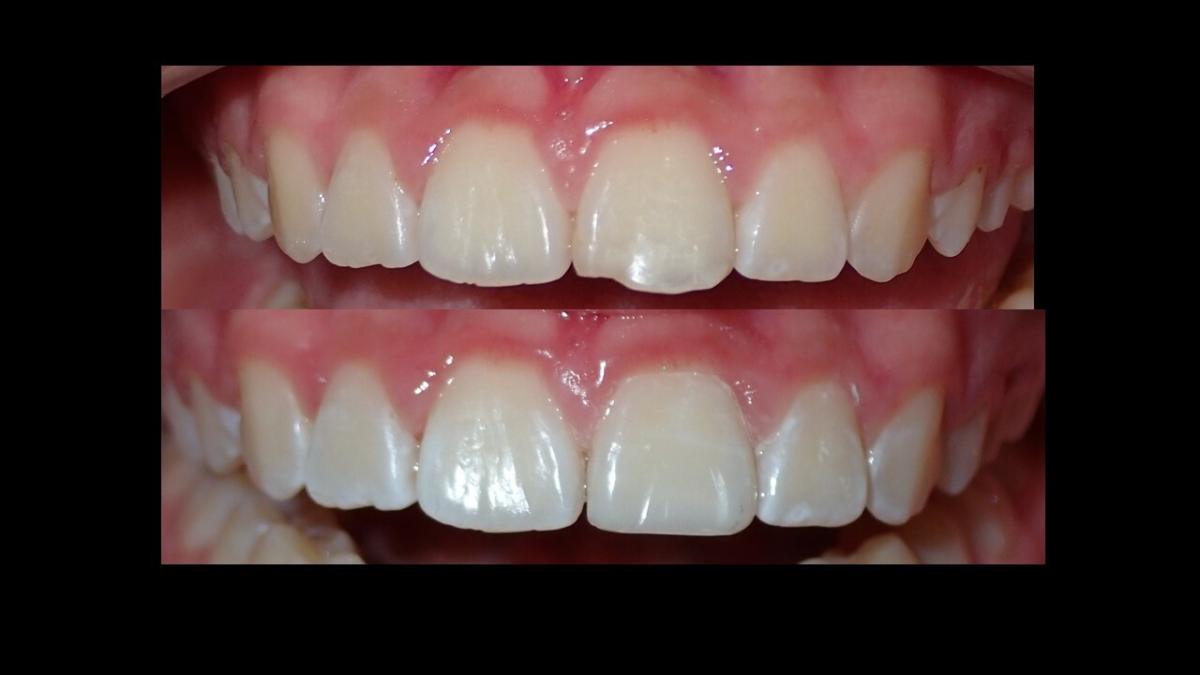

large-Fractura con resina

large-Fractura